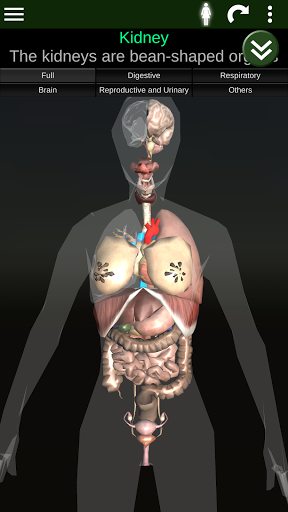

Показує 3D анатомічну модель основні органи людського тіла та опис кожного з них.

* Травна система, включаючи шлунок, тонку кишку, товсту кишку та анімацію цієї системи.

* Дихальна система, яка включає трахею, бронхи, легені та анімацію цієї системи.

* Репродуктивна система, яка включає чоловічі та жіночі репродуктивні органи.

* Мозок, який включає головний мозок, мозочок і стовбур мозку.

* Серце, що включає передсердя, шлуночки, аорту і одушевлення цього органу.

* Легкий доступ і навігація (масштабування, 3D-обертання).

* Порівняйте чоловічі та жіночі органи.